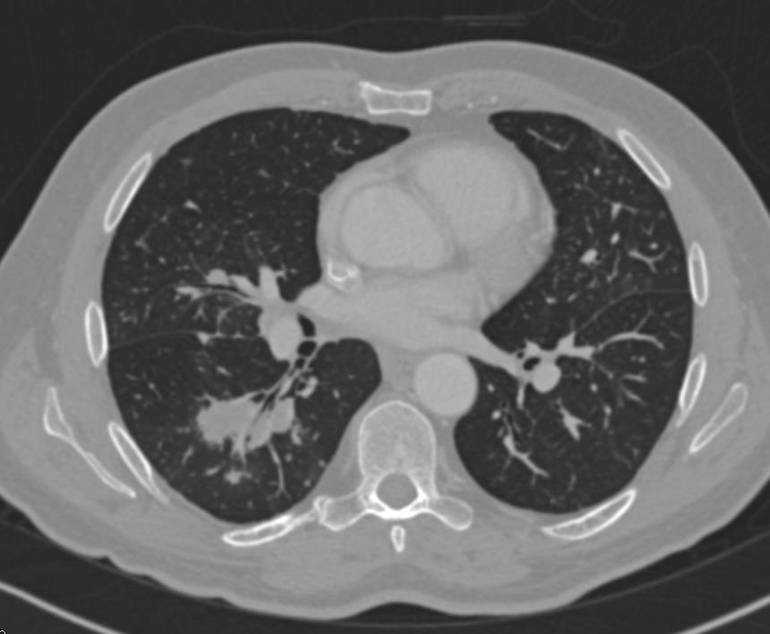

Процессы, затрагивающие нижние отделы дыхательной системы, в начале могут не проявляться специфическими симптомами и выявляются только с помощью рентгенографии. Позже в легких наблюдаются прогрессирующие деструктивные изменения паренхимы (ткани альвеол) в виде множества очагов, пораженных гранулематозом. Эти поражения сопровождаются болями в груди и выраженной одышкой и могут привести к выпотному плевриту и респираторной недостаточности.

Раннее выявление гранулематоза представляет собой сложную задачу, поскольку на начальных этапах пациенты часто принимают симптомы заболевания за обычную простуду или грипп и редко обращаются за медицинской помощью. Первым шагом в диагностике является тщательный опрос и осмотр пациента для выявления симптомов. При наличии подозрений на болезнь Вегенера рекомендуется консультация у ревматолога, а также проведение лабораторных и инструментальных исследований, таких как рентгенография, ультразвуковое обследование и томография.